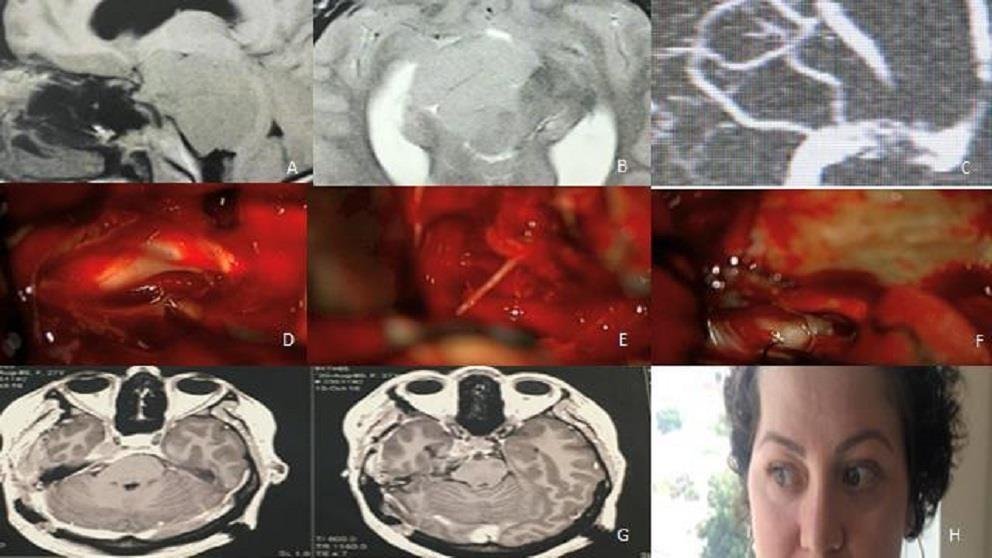

Figura 2: El estudio de la posición del tumor en el clivus, y la extensión o no de éste en la fosa media, sirve para decidir el abordaje. Para los tumores con un componente solo en el clivus superior, se utilizó un abordaje pterional pretemporal, abriendo la muesca de la carpa y eliminando el tumor del clivus superior que estaba comprimiendo el nervio trigémino y causando neuropatía (A). Para este meningioma esfenopetroclvial anaplásico se utilizó el abordaje craneo-órbito-cigomático con petrosectomía anterior con extirpación tumoral. El paciente se sometió previamente a cirugía con ojo congelado (frozen eye) (B). El abordaje petroso posterior (pre-sigmoide supra / infratentorial) se usa para meningiomas petroclivales con extensión tumoral en la fosa media (C, D, E). Para los meningiomas petroclivales localizados completamente en la fosa posterior, el abordaje retrosigmoideo es suficiente independientemente del tamaño del tumor (F, G, H, I, J).

Figura 14: El abordaje petroso posterior está indicado para meningiomas petroclivales con inserción en el clivus medio y superior (A) y extensión en la fosa media (B). La venografía por resonancia magnética muestra el drenaje de la vena de Labbé en la unión de los senos transverso y sigmoideo (C). Imagen intraoperatoria del nervio oculomotor (D) y troclear (E) después de la resección del tumor. El facial está dentro del bloque óseo (*) y no necesita exponerse (F). Resonancia magnética con gadolinio postoperatorio (G y H). Paciente sin paresia postoperatoria de los nervios craneales (I).